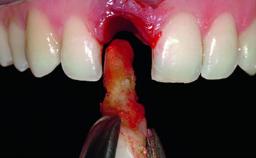

A healthy 38-year-old male patient was referred for replacement of a failing tooth-supported cantilever fixed dental prosthesis on teeth 11 and 21. The patient reported a history of trauma at 13 years of age that had resulted in the subsequent loss of tooth 11, as well as endodontic treatment of the adjacent abutment tooth 21. A metal-ceramic cantilever fixed dental prosthesis replacing tooth 11 had been provided by his general dentist several years after the loss of the tooth, with tooth 21 as the sole abutment. At the time of initial presentation, this restoration had been in service for over 20 years.